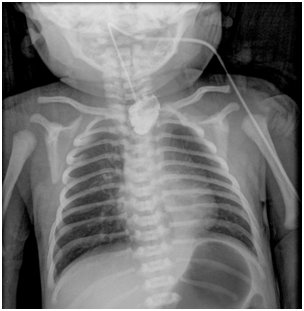

【109-2 醫學(五) 第44題】

一名33週的早產兒,出生後生命徵象穩定,但在第一次餵奶時發現有咳嗽、嗆到、發紺的狀況,且伴隨著大量口水流出;當試著置入胃管時,發現無法放至胃部,因此新生兒科醫師安排食道鋇劑攝影如圖。針對上述情況,下列相關敘述何者錯誤?

A 該患兒必定伴隨著食道氣管瘻管(tracheoesophageal fistula) B 該患兒很可能身體有其他的異常,因此一定要再檢查其他器官系統有無異常 C 該患兒之疾病以Gross type C最常見 D 若沒有其他更緊急的狀況,患兒應儘速接受手術治療